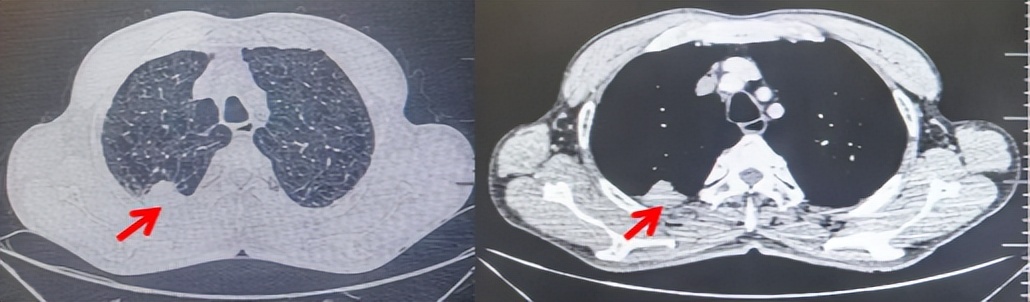

69岁男性,无糖尿病、高血压、心脏病等基础疾病,无吸烟、饮酒史,无肿瘤家族史。2023.06.07行胸部CT检查:右肺上叶胸膜下见肿物影,大小约33mm×22mm,边缘可见分叶,考虑恶性病变可能性大,双肺间质改变(如图1)。2023.06.14行“单孔胸腔镜下右肺上叶切除、肺门及纵隔淋巴结清扫、胸膜粘连松解术”;术后病理:(右肺上叶)腺癌(低分化,实体型占60%,不良腺体占40%),局灶伴神经内分泌标记表达(CD56、Syn),可见STAS及胸膜侵犯,未见确切神经侵犯及脉管内癌栓;(气管切缘)净;(淋巴结)未见转移癌0/26(2组0/2;4组0/6;7组0/2;对侧7组0/8;10组0/2;11组0/3;12组0/2;13组0/1)。术后分期pT2aN0M0 IB期,术后NGS基因检测:无驱动基因突变,PD-L1(22C3)TPS<1%。术后定期复查。

2024.11.19患者出现右侧胸痛,复查胸部CT检查示右侧胸膜肿物,大小约31mmX24mm,右侧4、5肋骨骨质破坏,考虑转移(如图2)。建议患者穿刺活检取病理明确诊断,患者拒绝,经MDT会诊后结合影像学表现及病史考虑为胸膜转移,肋骨转移,分期为rT0N0M1a IVA期,DFS仅仅17个月。2024.12.05起行信迪利单抗联合培美曲塞+卡铂方案治疗4周期,复查胸CT评效PR(如图3)。之后给予信迪利单抗+培美曲塞维持治疗6周期,期间复查CT评效PR(如图3)。目前信迪利单抗+培美曲塞维持治疗中,截止至目前PFS约为8个月,治疗期间未出现明显毒副反应。

图1:患者手术前(2023.06)胸部CT肺窗及纵隔窗

图2:患者胸膜及肋骨转移(2024.11)胸部CT肺窗、纵隔窗及骨窗